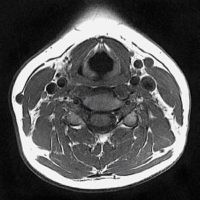

iRM Regiune Cervicala (Gât)

Examinarea iRM a regiunii cervicale/gatului deceleaza leziuni ale faringelui, laringelui, esofagului cervical, ale glandelor submandibulare, parotide si ale glandei tiroide precum si prezenta adenopatiilor de la acest nivel.